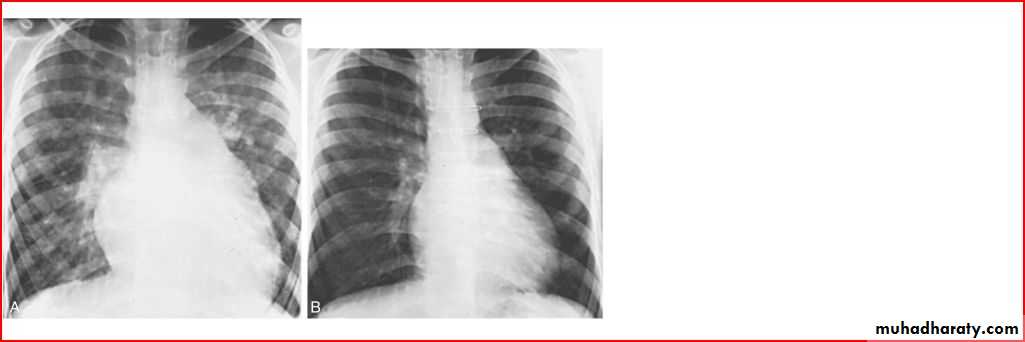

dextrocardia with situs inversus

Homgenous opacity filling the rt. Hemithorax there is shefting in trachea to rt. Side mean this is collapse

A showing normal x rayB xray during expiration showing lt. lung emphysema make shifting of mediastinum

Opacification of whole lt. hemithorax consolidation of pneumonea but no pleural effusion b.c there is free costophrenic angle